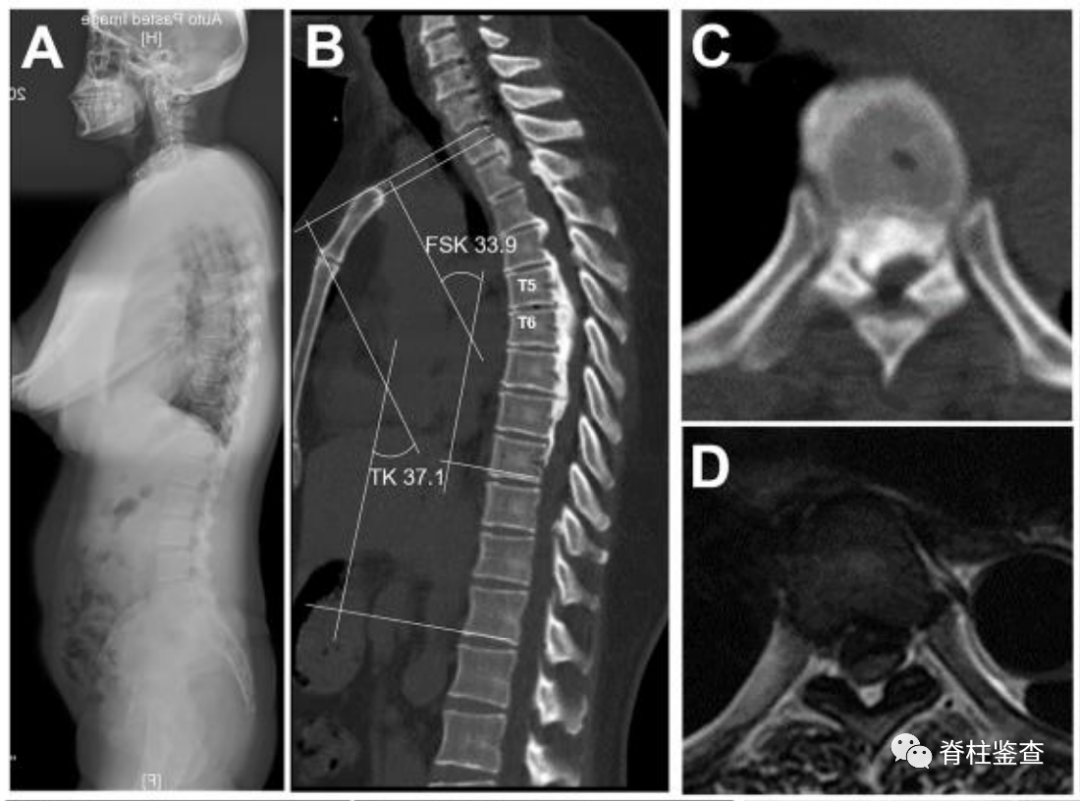

49岁女性,多节段胸椎后纵韧带骨化

(A)术前全脊柱的X线。(B) 术前全脊柱CT显示多节段后纵韧带骨化。(C) 轴位CT显示,70.6%的椎管被占据。(D) 轴位MRI显示脊髓受压和形态学改变。(E) 矢状位MRI显示胸椎管狭窄。(F) 术中显示脊髓的纵向张力(蓝色箭头)。(G) 脊柱缩短后,张力解除,脊髓变得松弛(蓝色箭头)。